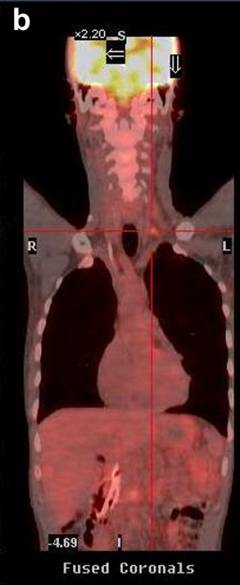

A 51-year-old Caucasian male presented with a history of progressive jaundice, loss of weight, acholic stools, and bilirubinuria. He was found to have a pancreatic head mass on a transabdominal ultrasound and CT scan of the abdomen. Fine needle aspiration cytology (FNAC) of the pancreatic mass confirmed well-differentiated ductal adenocarcinoma. The patient had unresectable disease given that the tumor encased approximately 180 degrees of the superior mesenteric artery. The initial CT scan of the abdomen showed nodules in the liver that were suspicious but not confirmatory for metastasis. Therefore, PET/CT scan was performed where no liver metastases were noted. CT scan of the neck did not demonstrate any evidence of supraclavicular metastasis (Figure 1). However, there was uptake of 18-fluorodeoxyglucose (FDG) with a standard uptake value (SUV) of 4.3-4.7 in the medial left supraclavicular region that was suspicious for nodal metastasis (Figures 2 and 3). FNAC of the left supraclavicular lymph node showed poorly differentiated metastatic adenocarcinoma consistent with a pancreatic primary. Therefore, the final clinical staging was stage IV (T4NXM1, Table 1).

Figure 3. PET/CT scans of Patient #1 before (a.) and after (b.) chemotherapy showing supraclavicular metastasis. After 5 cycles of chemotherapy, PET/CT scan (b.) shows favorable response to therapy with decrease in SUV of supraclavicular lymph nodes from 4.3-4.7 (baseline, a.) to 2.4 (b.). |

After confirmation of metastatic disease, the patient was started on gemcitabine 1,000 mg/m2 and nab-paclitaxel 100 mg/m2, both intravenously (i.v.) on days 1, 8, and 15 with cycles repeated every 28 days. At the most recent presentation, the patient had completed five cycles of systemic chemotherapy with gemcitabine and nab-paclitaxel. His CA 19-9 level had declined from 962 U/mL at baseline to 444 U/mL (reference range: 0-55 U/mL) and his PET/CT and CT scans demonstrated a favorable response to therapy. Notably, his PET/CT scan showed a decrease in SUV in the left supraclavicular nodal metastasis from 4.3-4.7 at baseline to 2.4 (Figure 3).

In all of the three cases reported in this article, PET/CT scans detected supraclavicular lymph node involvement that was not identified by the standard imaging protocol, CT scan of the chest and abdomen, for pancreatic cancer. Of note, CT scans, which are the de facto surveillance imaging modality, failed to detect metastasis in all three cases (Figure 1). Of course, this was predominantly due to the fact that CT scans of the neck would not be part of a routine surveillance algorithm for patients with pancreatic cancer.